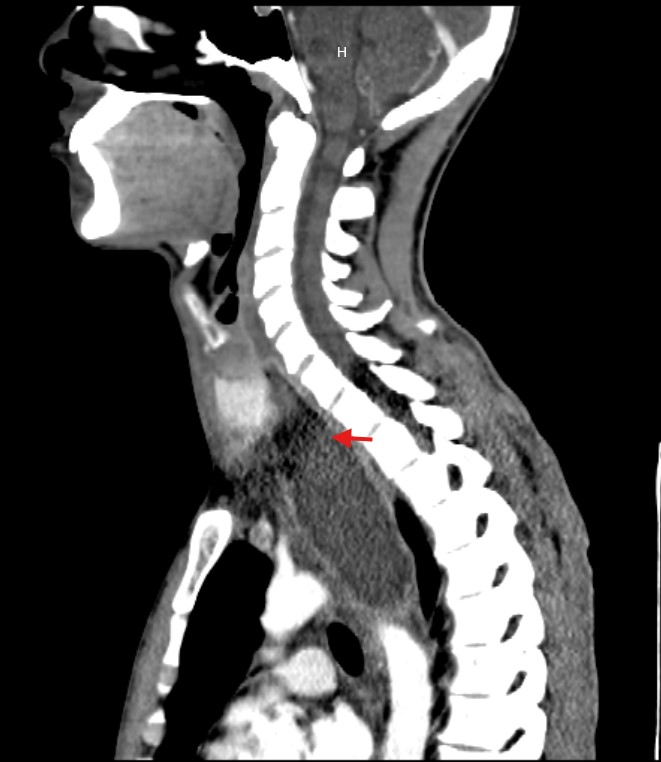

Due to the unclear etiology of the symptoms, combined with unremarkable initial studies and the subsequent development of dyspnea, a CT scan of the neck and thorax was performed. This revealed a large collection centered in the mediastinum, dissecting tissue planes and extending below the carina, reaching into the neck up to the left thyroid lobe. Gas was observed both within the collection and around the thyroid gland and mediastinum, with the esophagus displaced to the right by the mass effect of the abscess (Figure 1-5).

Figure 1 CT: Sagittal view showing an abscess extending from the left thyroid space to the superior mediastinum.

Figure 2 CT: Sagittal view showing mediastinal abscess extension up to the bronchial bifurcation.